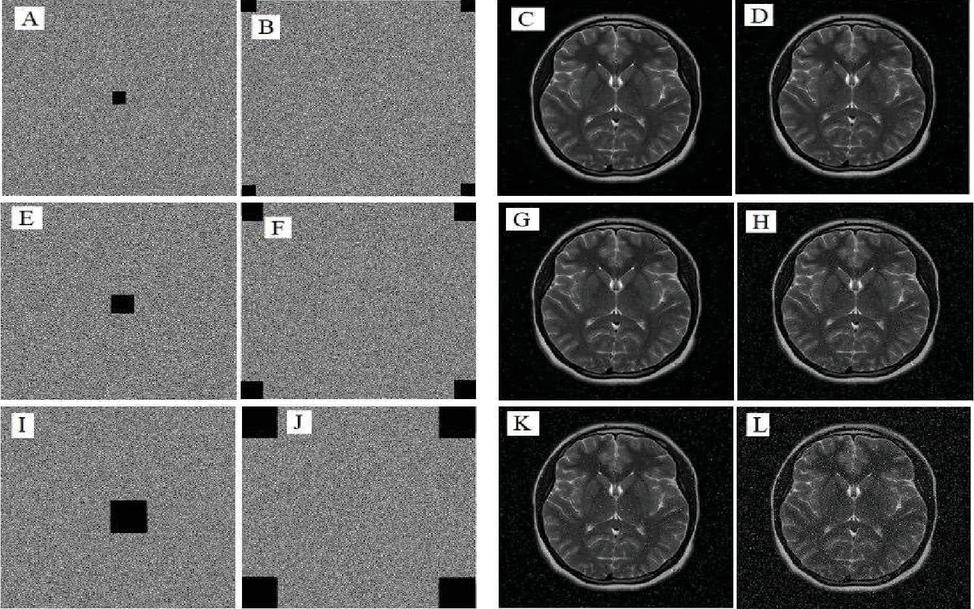

5.7 Examination of Robustness Against Occlusion Attack

An efficient encryption algorithm must be highly resistant to Occlusion attacks in order to avoid their detrimental effects on the image content during decryption. To evaluate the algorithm’s resistance to Occlusion attacks, it was assumed that a 512-by-512 brain image was subjected to Occlusion attacks of varying intensities and that the image used for decryption contained missing data. Figure 9 demonstrates the ability of the proposed encryption algorithm to thwart the Occlusion attack and mitigate its negative impact, as slight effects of the blockage attack can be seen on the decrypted images. Still, they remain legible to the human eye.

images

Figure 9 Depicts the outcomes of occlusion attacks on the medical brain image, where (A, B) are encrypted images with loss data sizes 16 × 16 pixels per square, (C, D) are the decrypted images with PSNR of 34.0479 and 29.3971, respectively, (E, F) are encrypted images with loss data sizes 32 × 32 pixel per square, (G, H) are the decrypted images with PSNR of 29.2848 and 23.9673, respectively, (I, J) are encrypted images with loss data sizes 64 × 64 pixel per square, and (K, L) are the decrypted images with PSNR of 23.7947 and 17.9201, respectively.